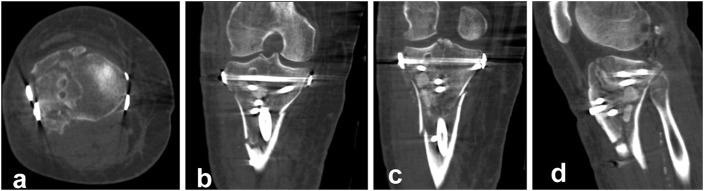

The present report describes a retrospective and prospective study of all 17 patients (age range, 25 to 75 years) who were admitted under the author's care for the treatment of a closed, bicondylar tibial plateau fracture between 2013 and 2015. All patients consented to undergo fixation of the fracture with intramedullary nailing through a suprapatellar approach and with use of condylar bolts. The reconstructed articular surface was supported with freeze-dried allograft that had been previously soaked in concentrated bone marrow. The patients were followed at regular intervals, and the results were assessed with the Knee injury and Osteoarthritis Outcome Score (KOOS).

All patients were followed for at least 1 year (average and standard deviation, 25.23 ± 8.95 months; range, 12 to 46 months). All fractures united clinically and radiographically between 10 and 22 weeks (average, 15.1 ± 2.91 weeks), with no instances of neurovascular complication, infection, or implant failure. One patient underwent early revision of the fixation because of unsatisfactory reduction of the articular surface, and 1 patient had secondary fracture displacement. One condylar bolt was removed after fracture healing because of irritation at the insertion site. However, all patients regained knee motion without physiotherapy and all were fully weight-bearing by the fifth postoperative month.

本报告描述了一项回顾性和前瞻性研究,研究对象为2013年至2015年间在作者治疗下因闭合性双髁胫骨平台骨折入院的所有17例患者(年龄范围25至75岁)。所有患者均同意采用髌上入路髓内钉固定并使用髁螺栓固定骨折。用预先浸泡在浓缩骨髓中的冻干同种异体骨支撑重建的关节面。定期对患者进行随访,并采用膝关节损伤和骨关节炎疗效评分(KOOS)评估结果。

所有患者均随访至少1年(平均和标准差,25.23±8.95个月;范围,12至46个月)。所有骨折在10至22周(平均,15.1±2.91周)临床和影像学上均愈合,无神经血管并发症、感染或植入物失败的情况。1例患者因关节面复位不满意而早期进行了内固定翻修,1例患者出现二次骨折移位。1枚髁螺栓在骨折愈合后因插入部位刺激而取出。然而,所有患者未经物理治疗即恢复了膝关节活动,且在术后第五个月时均完全负重。